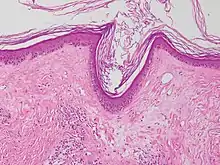

Interface dermatitis with lichenoid inflammation

| Generally/Not otherwise specified | Typical findings:[2]

| Lichen planus | Irregular epidermal hyperplasia with a jagged “sawtooth” appearance, compact hyperkeratosis or orthokeratosis, foci of wedge-shaped hypergranulosis, basilar vacuolar degeneration, slight spongiosis in the spinous layer, and squamatization. The dermal papillae between the elongated rete ridges are frequently dome shaped. Necrotic keratinocytes can be observed in the basal layer of the epidermis and at the dermal-epidermal junction. Eosinophilic remnants of anucleate apoptotic basal cells may also be found in the dermis and are referred to as “colloid or civatte bodies”. Whickham striae are usually seen in the areas of hypergranulosis. Vacuolar degeneration at the basal layer may be noted leading to focal subepidermal clefts (Max Joseph spaces). Squamatization occurs as a result of maturation and flattening of cells in the basal layer. It happens in areas of marked hypergranulosis with prominence of the sawtooth pattern of rete ridges. Wedge-shaped hypergranulosis can occur in the eccrine ducts (acrosyringia) or hair follicles (acrotrichia). In the hypertrophic subtype, the associated hyperkeratosis, parakeratosis, hypergranulosis, papillomatosis, acanthosis, and hyperplasia markedly increased with thicker collagen bundles forming in the dermis. Moreover, the rete ridges are more elongated and rounded as opposed to the typical sawtooth pattern. In atrophic LP, loss of the rete ridges and dermal fibrosis is prominent. In vesiculobullous LP, the disease progression is quicker. Hence, some of the distinctive features such as hyperkeratosis, hypergranulosis, or dense lymphocytic dermal-epidermal infiltrate may not be present. LP lesion may resolve with residual hyperpigmentation caused by a persistent increase in the number of melanophages in the papillary dermis.[9] | ![]() | ![]() |